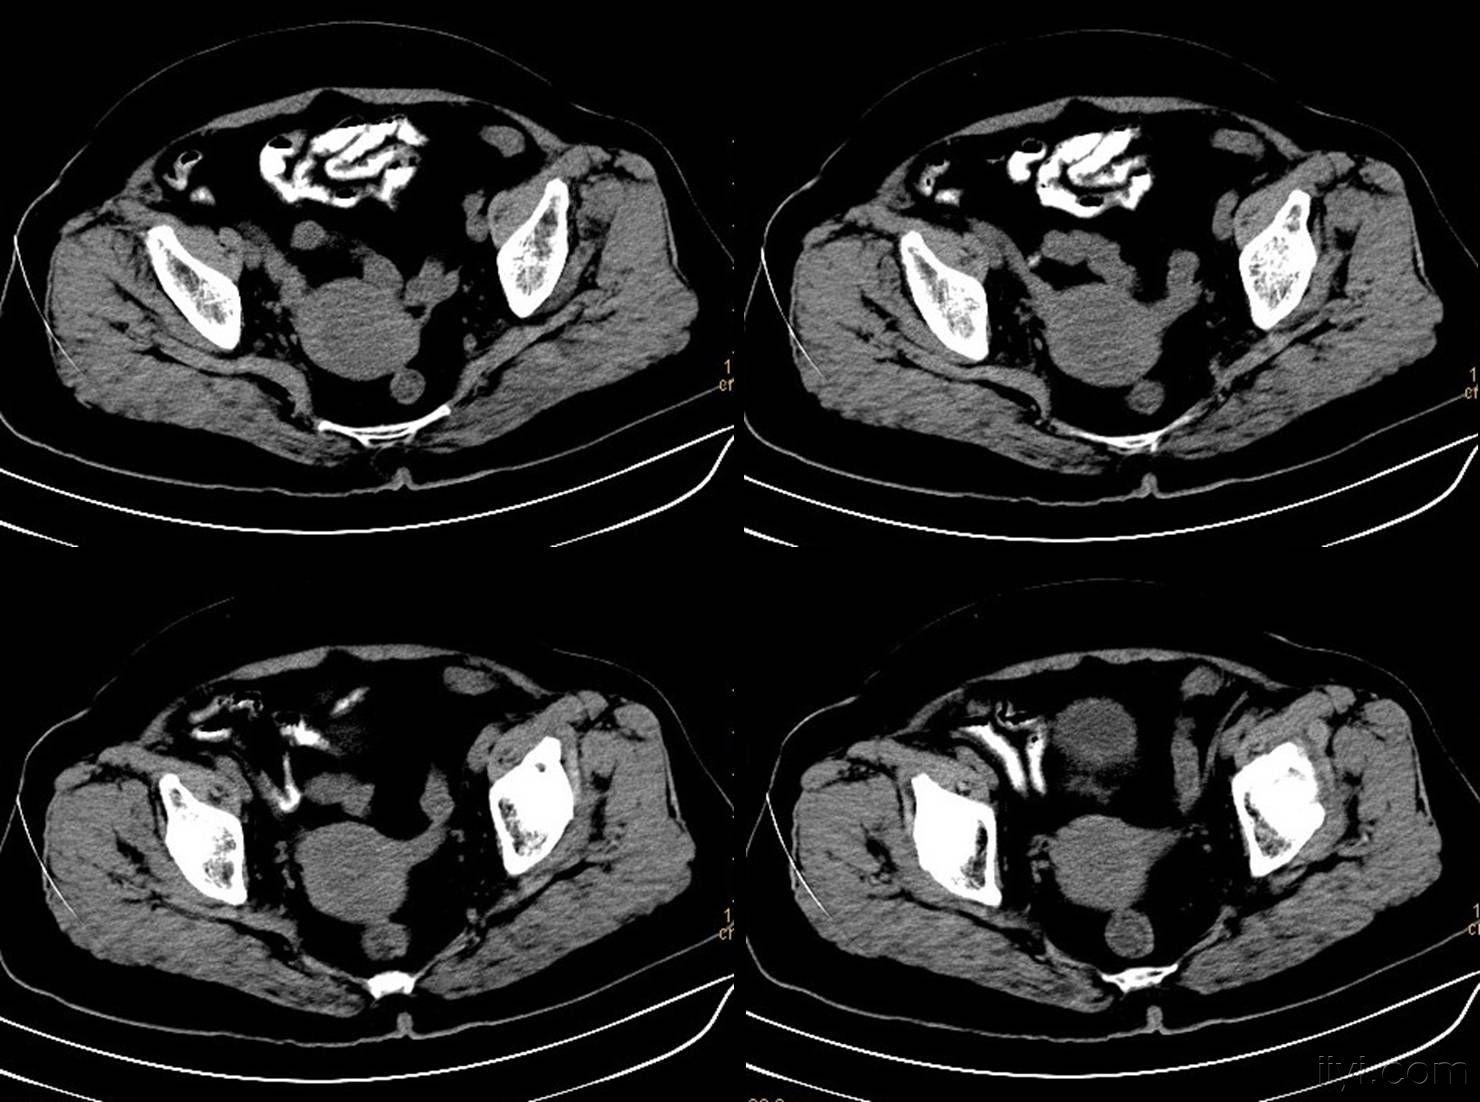

正常盆腔ct,盆腔ct图解

盆腔ct图解

正常女性盆腔ct图谱

盆腔ct图片

正常女性盆腔ct图片

正常女性盆腔ct影像图

盆腔CT

女性盆腔CT

盆腔ct图片详解

男性盆腔ct解剖图

女性盆腔CT影像